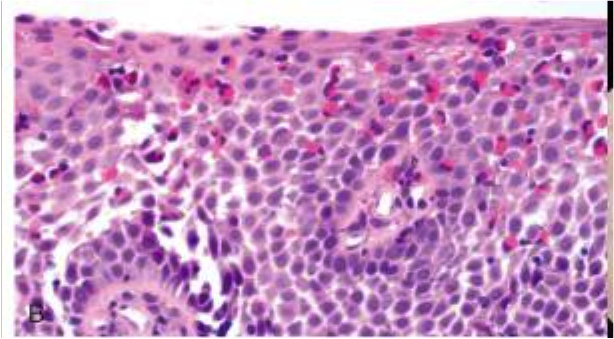

herpes esophagitis

lateral margin of ulcer

cowdry A intranuclear inclusions (Multinucleation, chromatin Margination, nuclear Molding)